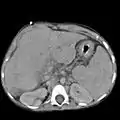

Abdominal CT, showing Morison's pouch as the dark margin surrounding the right kidney (at lower left corner of image)